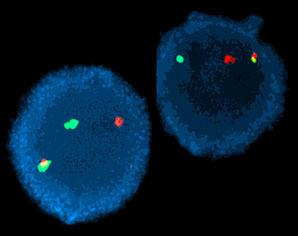

t(9;22) creates the Philadelphia chromosome (Ph1) and the BCR/ABL1 chimeric gene, the molecular basis of the disease

- Detectable by cytogenetics (karyotype, FISH) or molecular genetics (RT-PCR)

Genetics

95% w/ t[9:22], bcr-abl, on the Philadelphia chromosome

- BCR (breakpoint cluster region) gene on 22q11.2 fuses c ABL (Abelson, for a leukemia virus that carries similar protein) gene on 9q34

-- may have cryptic fusion requiring FISH

- this usually causes inc tyrosine kinase activity

Cytogenetics: t(9;22) on conventional karyotype

FISH: Fusion of BCR and ABL1 probes

Moelcular: RT-PCR demonstration of BCR-ABL1 fusion

Rare cases may have cytogenetically cryptic BCR-ABL1 rearrangement

CML: FISH major breakpoint; Red=ABL, Green = BCR